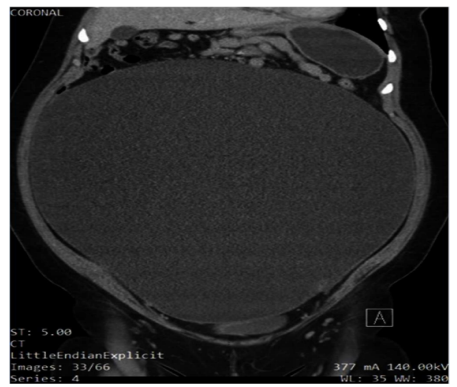

On examination, the patient appeared to be obese, welldeveloped, anxious, and cooperative. She was not able to tolerate a speculum examination due to the pain. There was no pulsatile abdominal mass, guarding of the abdomen, nor any generalized and/or rebound tenderness or rigidity. The lower left quadrant of the patient’s abdomen was tender with mild distention and normal bowel sounds were heard. An elevated blood pressure on admission (145/89) was noted. The urinalysis was unremarkable. Blood analysis showed hypochromic, microcytic anemia (10.3 g/ dL) with +1 anisocytosis (generally associated with iron deficiency anemia [11], and mild elevated chloride (109 mEq/L) and elevated glucose (109 mg/dL) levels. A pelvic ultrasound reported a normal uterus with no endometrial abnormalities, and the right ovary appeared normal. The left ovary was not visualized (Figures 1 and Figure 2). A large cystic structure was seen, whose origin was unknown. An abdominal/pelvic computerized tomography (CT) with contrast found a 36 cm cyst lesion filling the abdominal and pelvic cavity which appeared to originate from the left adnexa with a complicated hyperdense fluid or debris focus noted in the inferior margin of the cyst (Figure 3). The surrounding structures appeared unremarkable. There was a trace amount of fluid in the Pouch of Douglas. (Figure 4).

Figure 2: Ultrasound image showing the cyst’s complex blood supply. This complexity raised suspicion for malignancy